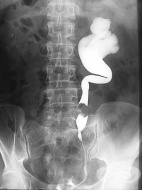

Медицинските изследвания са вид медицинска манипулация, която има за цел да открие, диагностицира или оцени различни заболявания или склонност към тях, както и ефекта от проведената терапия. Тези изследвания могат да бъдат диагностични, скринингови или с оценителен характер.

Диагностичните изследвания се използват за потвърждаване на диагноза или за откриване на причината за дадено заболяване въз основа на данните от симптомите. Такива диагностични изследвания са например изследването на кръвната захар при пациенти със съмнение за захарен диабет, изследване на пълна кръвна картина при пациенти с висока температура и съмнение за бактериална инфекция, назначаване на електрокардиограма при болка в гърдите за откриване на сърдечни нарушения.